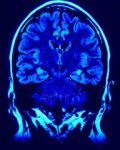

Die Hypophyse und die Bedeutung für die naturheilkundliche Behandlung

Die Bedeutung der Hypophyse und dem damit eng verknüpften Hormonsystem mit seinen jeweiligen Auswirkungen für den Gesamtorganismus ist für die naturheilkundliche Behandlung/Therapie von besonderer Bedeutung. Kaum jemand kann die Hypophyse einordnen und doch können die Auswirkungen auf den Menschen enorm sein, sollte sie ihre Arbeit nicht wie geplant verrichten. Was ist die Hypophyse? Die Hypophyse … Die Hypophyse und die Bedeutung für die naturheilkundliche Behandlung weiterlesen